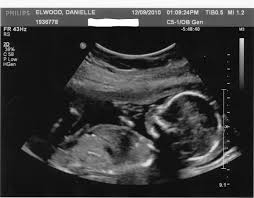

• ثالثاً : جهاز الموجات الفوق صوتية - UltraSound

يستخدم التصوير باستخدام التخطيط التصواتي وهي موجات صوتية ذات تردد عال يتراوح بين 2 إلى 10 ميغاهرتز والتي تنعكس من قبل أنسجة الجسم بزوايا مختلفة لتنتج صوراً ثنائية الأبعاد عادة على شاشة المرقاب. غالباً ما تستخدم هذه الطريقة لمراقبة الجنين عند النساء الحوامل.

صورة للتصوير الطبي :